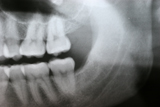

Wisdom Tooth Removal

Sometimes wisdom teeth are not functional, but instead create swelling and pain in the surrounding soft tissue, and they need to be taken out.

During the development of wisdom teeth, they often push away their neighboring teeth and contribute to anterior teeth crowding. Therefore, extraction of wisdom teeth is recommended in their early stage of eruption to prevent anterior crowding. The stress of eruption of wisdom teeth that grow horizontally causes dental decay on the 2nd molars and extraction is recommended before dental decay initiates.

Before / After